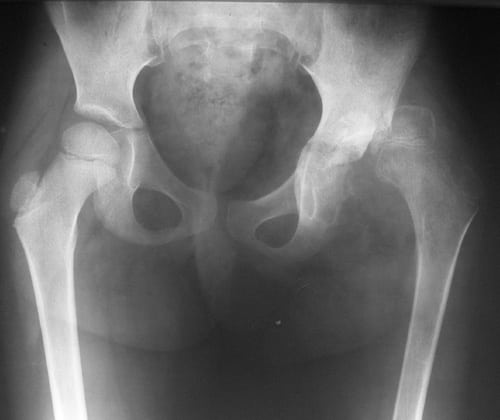

У половины пациентов остеохондрома обнаруживается в дистальном или проксимальном концах бедренной кости. У остальных 50% больных новообразованиями оказывались поражены и другие отделы скелета.

На рентгенографических изображениях хорошо просматриваются измененные контуры бедренной кости. Визуализируются и очертания новообразования — четкие, непрерывные. С помощью рентгенологического исследования не удается рассмотреть сформировавшуюся хрящевую оболочку, только если в ней нет очагов кальцификации. При подозрении на укрупнение хрящевого слоя пациентам назначается МРТ.

Дифференциальная диагностика проводится для исключения остеомы, паростальной остеосаркомы, паростальной костно-хрящевой пролиферации и хондросаркомы, возникающей вследствие озлокачествления остеохондромы.